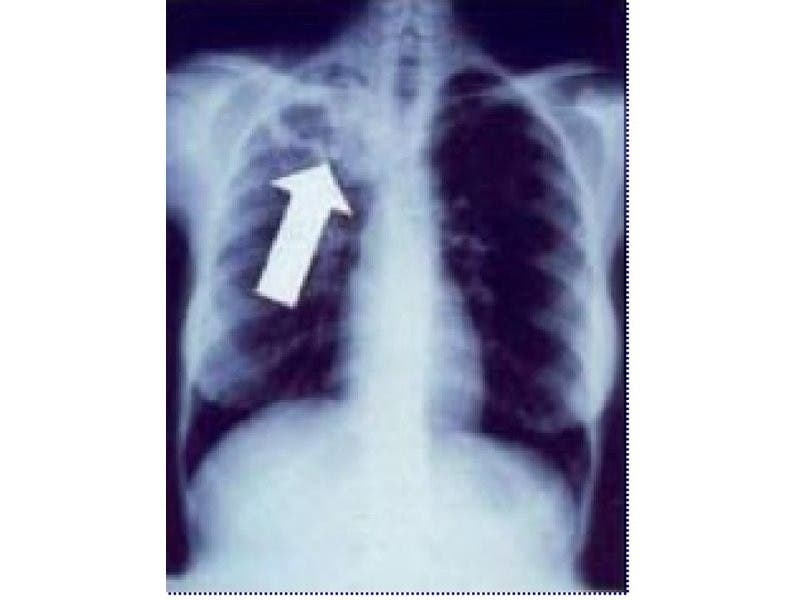

Tuberculosis can affect a person’s lungs, brain, kidneys and spine, according to the Centers for Disease Control. It can be fatal and is spread through the air, such as when a person coughs or sneezes. Most cases are treatable with common medications.

Tuberculosis is not easily transmissible and XDR-TB, in particular, is also rare, health officials said. XDR-TB is a form of the disease that is resistant to many of the most powerful anti-TB drugs.